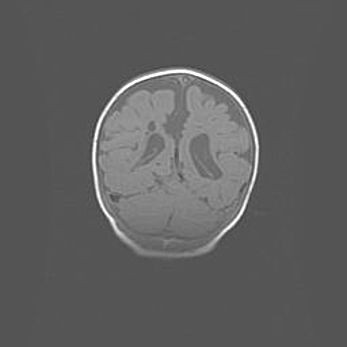

Открытая гидроцефалия.

Возраст: 9 месяцев 12 дней

Вес: 6800 г

Пол: мужской

Окружность головы: 41,5 см

Срок гестации: 28 недель

Гидроцефалия головного мозга у новорожденных имеет характерный признак: опережающий рост окружности головы приводит к визуально хорошо определяемой гидроцефальной форме сильно увеличенного в объёме черепа. Детские неврологи определяют следующие симптомы гидроцефалии у грудничков: выбухающий напряжённый родничок, частое запрокидывание головы, смещение глазных яблок к низу.